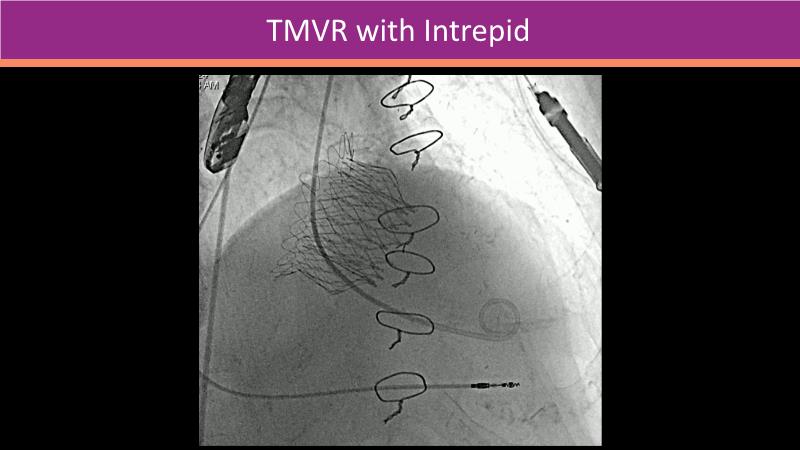

Explore the future of transcatheter mitral and tricuspid therapies in this innovative session. Learn how advanced imaging techniques like CT/fluoro fusion and 4D intracardiac echocardiography are revolutionizing complex procedures, enhancing both safety and outcomes. Hear from experienced operators as they share their insights on the evolving landscape of structural heart disease interventions and the tools shaping tomorrow’s treatments.

- To understand how innovative multi-modality imaging techniques can facilitate complex mitral and tricuspid valve procedures

- To learn how 4D ICE and CT/Fluoro fusion can improve procedural safety and efficiency